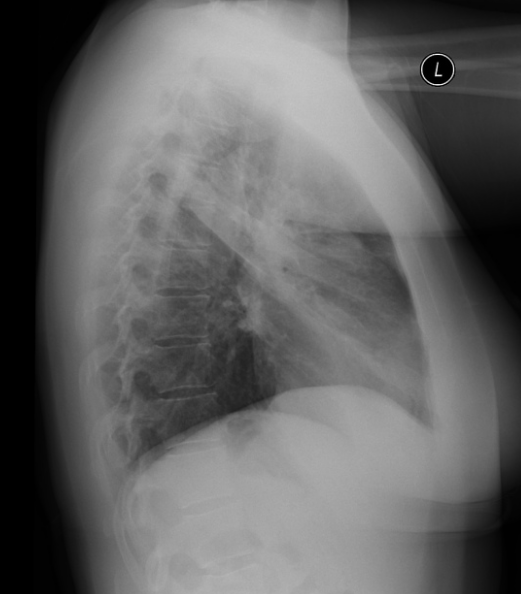

78세 여성이 발열, 호흡곤란, 그리고 가래 증상을 호소하며 내원하였다. 환자의 가슴 X선 사진이다. 이 환자의 폐 병변은 어디에 위치해 있는가?

발열과 호흡기증상이 있으며 CXR상 consolidation이 있어 폐렴이 의심된다. 좌측 폐에 병변이 있으며, lateral view에서 LUL임을 알 수 있다. Chest PA상 심장 좌측 경계가 불분명하게 관찰되므로 보기 중에서 병변의 위치를 LUL anterior segment로 짐작할 수 있다.